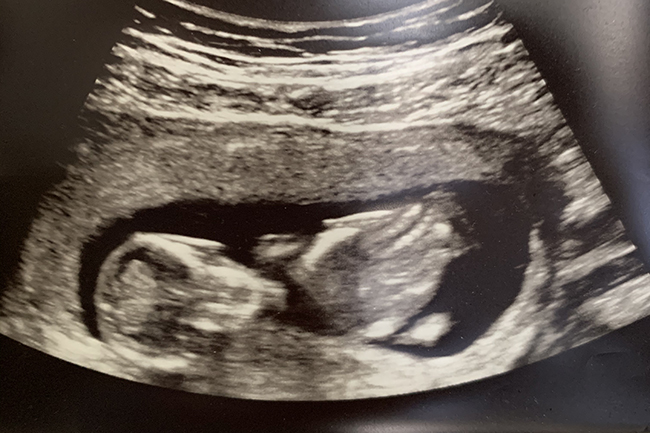

I felt a few little flutters for the first time at 16 weeks but it was very sporadic after that. It was hard not comparing it to Lyla's pregnancy where I felt her kick at 15 weeks and it was very consistent after that. It added to some anxiety I was working through but we had our anatomy ultrasound last week and it was a giant weight off my shoulders when we learned that baby is healthy and doing so well! As I suspected, I have an anterior placenta this time which is why I haven't felt the baby move consistently up until this point.

We had the sweetest and best ultrasound tech who explained every little detail of what she was looking at. Baby was practically bent in half and facing my spine most of the ultrasound (the position looked so uncomfortable!) and she had to keep bouncing the wand up and down on my stomach to see if she could get some movement to get the pictures she needed. We got to bring home so many cute profile pictures of that little tucked chin and tiny nose! Thanks to a moment of crossed legs and eventually the monitor being turned away, we made it out of there without finding out the gender ... a dream I've had with all of our pregnancies and I'm so excited for that surprise on delivery day!!! Nic joked that he was going to ask her to kick the garbage can for a girl or knock on the door for a boy on her way out of the room. haha He really wanted to know but there is just no way he could keep it from me without accidentally slipping up in some way, I just know it. I'm grateful he is on board with it being a surprise this time!